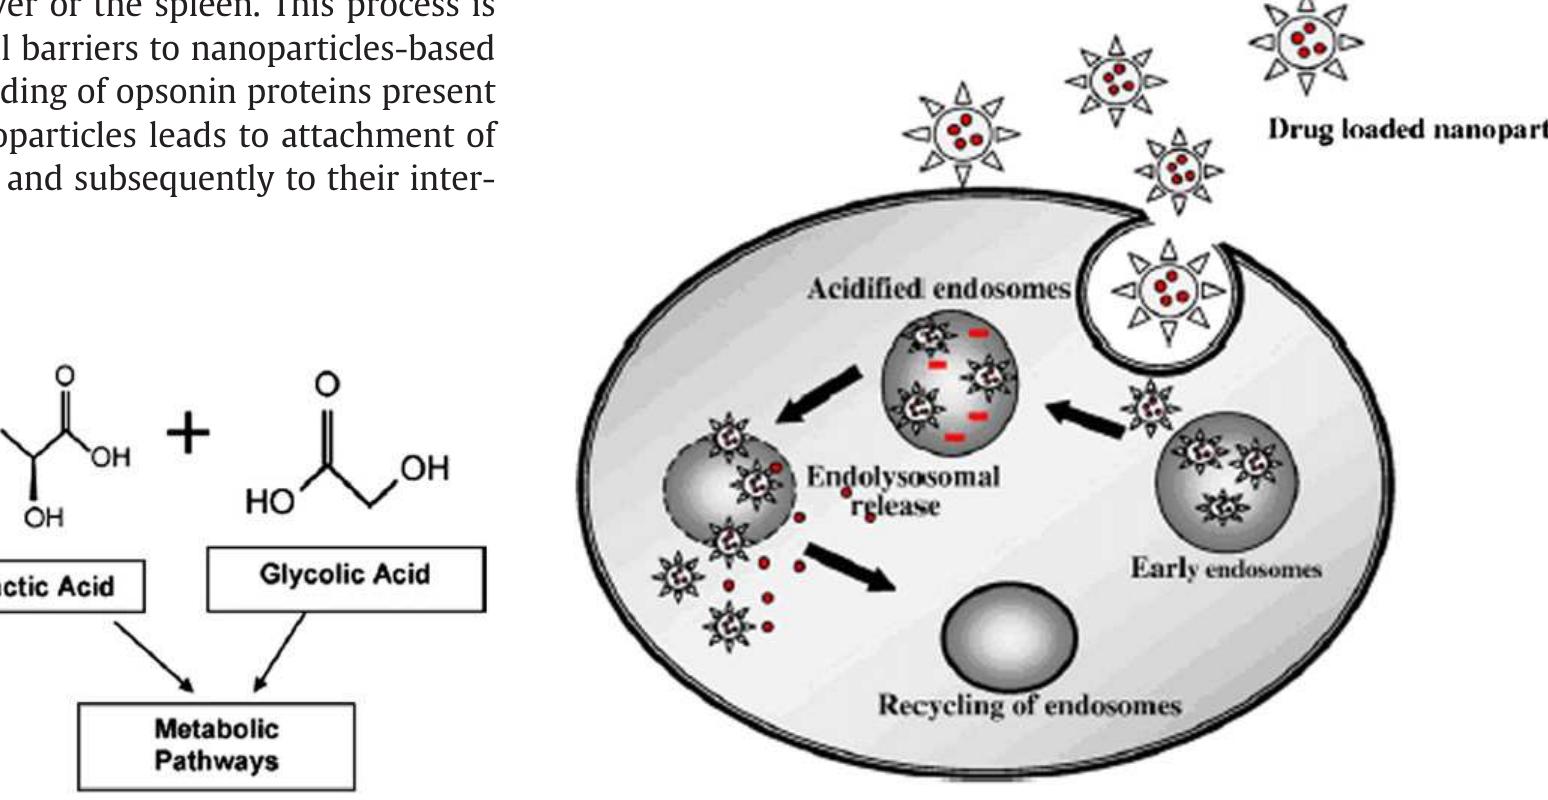

Poly(lactic-co-glycolic acid) (PLGA) is one of the most successfully developed biodegradable polymers. Among the different polymers developed to formulate polymeric nanoparticles, PLGA has attracted considerable attention due to its... more

![Fig. 2. Hydrolysis of PLGA nanoparticles: PLGA nanoparticles are biologically hydrolyzed in acidic medium into lactic and glycolic acid. These hydrolysis products have been metabolized in TCA cycle. PLGA nanoparticles have been mostly prepared by emulsification—-diffusion [46], solvent emulsion-evaporation [36], interfacial deposition [42] and nanoprecipitation method [47] (Fig. 3). Generally in emulsification-diffusion method, the PLGA polymers are dissolved in organic solvent (EtAc, MEK, PC, BA, etc.), poured and separated in aqueous phase having stabilizer and subsequently emulsified by homogenizer. In solvent evaporation method, the polymers are dissolved in volatile organic solvent (DCM, acetone, CHCl3, EtAc, etc.) and poured into continuously stirring aqueous phase with or without emulsifier/stabilizer and sonicated. Interfacial deposition methods have been used for the formation of both nanocapsule and nanospheres. The nanoparticles are synthesized in the interfacial layer of water and organic solvent (water miscible) and finally the nanoparticles are Polymeric nanoparticles have been synthesized using various methods [42] according to needs of its application and type of drugs to be encapsulated. These nanoparticles are extensively used for the nanoencapsulation of various useful bioactive molecules and medicinal drugs to develop nanomedicine. Biodegradable polymeric nanoparticles are highly preferred because they show promise in drug delivery system. Such nanoparticles provide controlled/sustained release property, subcellular size and bio- compatibility with tissue and cells [43]. Apart from this, these nanomedicines are stable in blood, non-toxic, nonthrombogenic, nonimmunogenic, noninflammatory, do not activate neutrophils, biodegradable, avoid reticuloendothelial system and applicable to various molecules such as drugs, proteins, peptides, or nucleic acids [11]. The general synthesis and encapsulation of biodegradable nanomedicines are represented in Fig. 1. The drug molecules either bound to surface as nanosphere or encapsulated inside as nanocap- sules.](https://figures.academia-assets.com/51115310/figure_002.jpg)